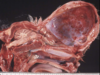

Name the pathologic process and which species this is considered “pathologic”.

Lissencephaly

Pathologic for any domestic mammal

Non-pathologic for some mammals & everything else that is not a mammal